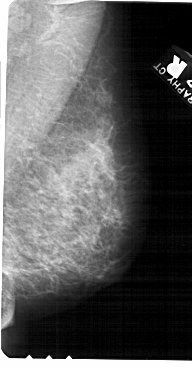

A_1555_1.LEFT_CC

LEFT_CC LINES 5491 PIXELS_PER_LINE 2731 BITS_PER_PIXEL 12 RESOLUTION 43.5 NON_OVERLAY